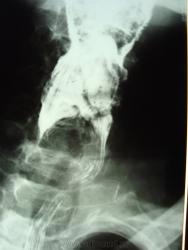

мужчина 1932 г.р. (лежачий пациент, инвалид) привезли со скорой на рентфию ОГК. случайно оказалась рядом и выяснила у сына, что он 3 дня не разговаривает и не кушает. Решила дать глоток бария пока лежит(снимки наспине), вот что получилось....

Образование или инородное тело?

С учетом таких контуров образования возможно лейомиома, но расположение странное, а может образование идет со стороны щитовидной железы?

наверно инородное тело врядли (большое какое то), может из щитовидки что то прорасло??? а может вообще заглоточный абсцесс????

Ну, у стариков инородное тело (кусок мяса) может дать интересные картинки.

Уж больно четкий кусочек мяса, с учетом если с зубами не все в порядке.

Тоже на все 100% соглашаюсь с Валентином Львовичем, в первую очередь необходимо исключать т.н. "мясной завал", а мясо там...сало ...или еще что - дело десятое.....